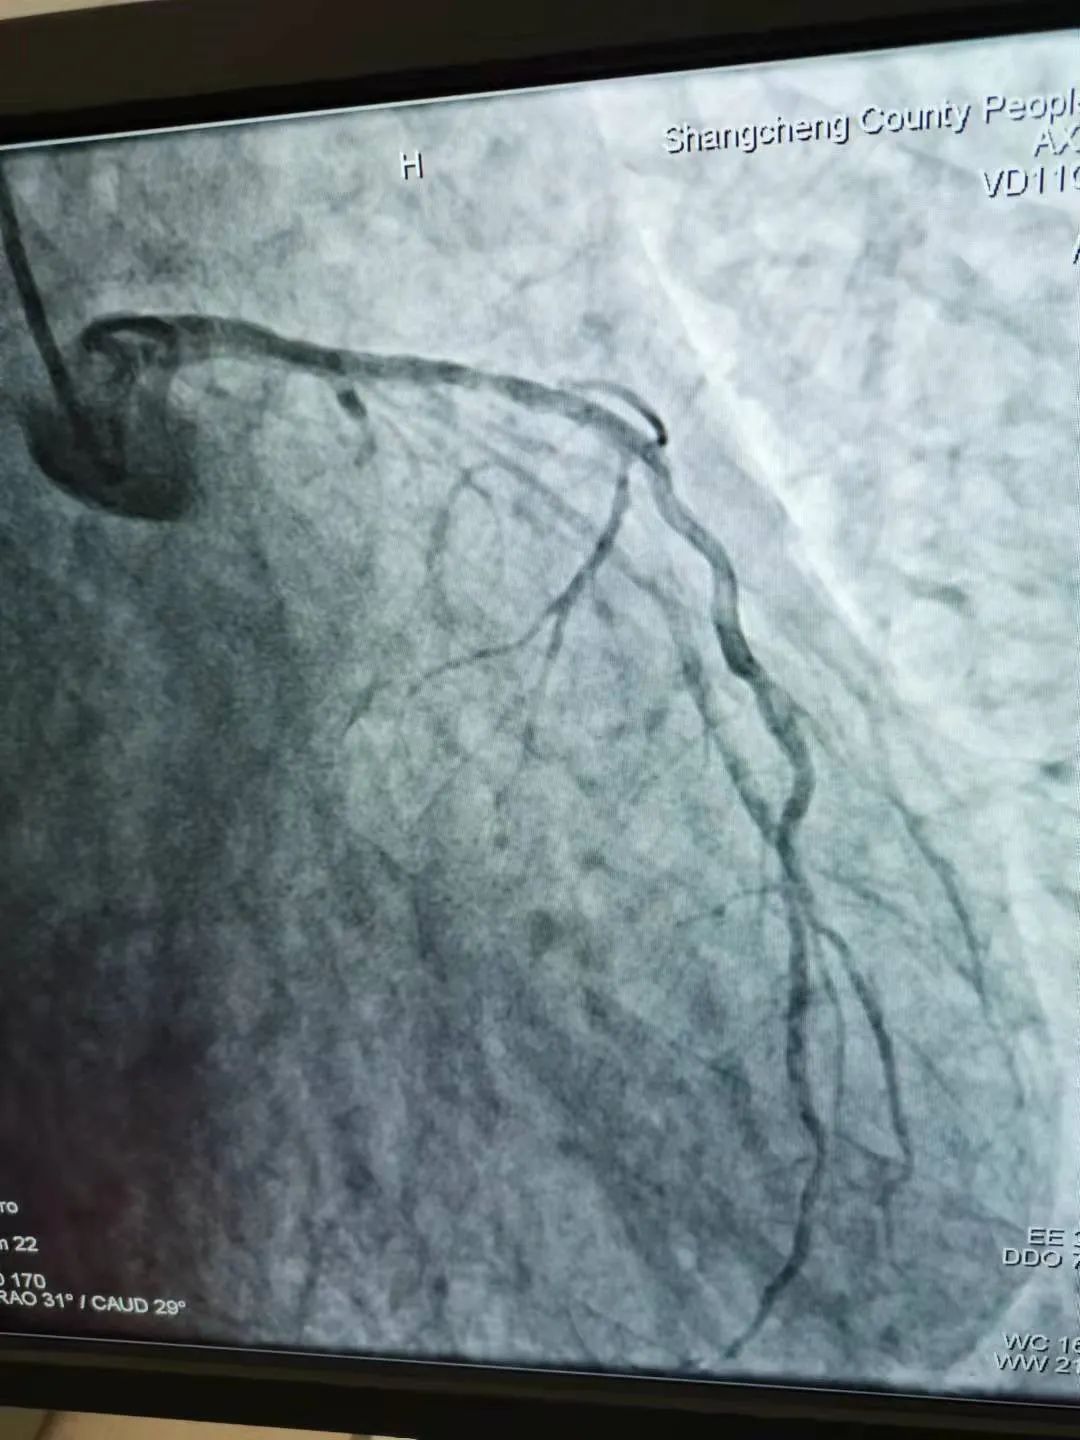

近日商城县人民医院心血管内科介入团队与"死神"赛跑,争分夺秒施术,成功救回一名77名急性心肌梗塞老人,这是我院独立、成功开展的第50例急诊PCI手术,是我院心脏介入技术发展过程中一个重要里程碑,标志着我院在急性心肌梗塞的诊疗技术日臻成熟,也显示出我院在介入治疗领域已具备较强的综合实力。 学科联动,无缝衔接,及时高效 2021年9月1日夜晚9时许,商城县人民医院胸痛中心建设群里上传了一份心电图检查报告,急诊医学科值班医师发来这样一条信息:“男性患者77岁,已胸痛4小时余,请心血管内科医师会诊”。心血管内科值班医师迅速作出判断后回复“急性下壁非ST段抬高性心肌梗塞、建议完善心肌标志物检查,请即刻跟患者家属谈话,建议尽快进行急诊介入治疗。”经过与家属成功沟通后,患者由急诊绿色通道被送往介入手术室,而心血管内科介入团队此时已火速到达了手术室,与此同时,心血管内科熊晨晖主任结合患者临床症状,并仔细查看患者的急查心电图及心肌标志物的检查结果后给出指导性意见:“患者年龄大,血流差,术中密切观察患者病情变化!”随后经介入团队密切配合,快速实施冠脉造影术及冠脉治疗术,患者病情由此转危为安,胸痛症状完全消失,30分钟后,手术顺利完成。该患者术后目前恢复情况良好。 术前心电图、心肌酶谱提示下壁急性心梗 冠脉照影结果及冠脉治疗后对比 什么是急诊PCI术 急诊PCI术是指在患者发生急性心肌梗塞后12小时内进行的冠状动脉血运重建,患者首先在导管室行冠状动脉造影术,找出冠状动脉“罪犯”血管及其病变部位,对病变部位行经皮冠状动脉腔内成形术和植入支架术,使闭塞的血管得以再通,从而改善心肌的血流灌注,使梗死的相关心肌得以及早的再灌注和功能恢复。因此,可以说,急诊PCI术为挽救急性心梗垂危的生命在最短的时间内构建了一条绿色通道,提高危重症病人的抢救成功率,且术后恢复快,患者生活质量能得到很大的提高。 坚守的力量:无论身在何处,电话就是命令! 商城县人民医院心血管内科于2018年10月开始在郑州大学第一附属医院、郑州大学第二附属医院专家的指导下开展了冠脉支架植入手术,至今已有500余例,自2021年3月以来,独立开展、完成急诊PCI手术50余例,效果良好,极大的提高了此类患者的救治率,降低了死亡率和致残率。一台台成功的手术、一个个因救治及时而重获新生的患者,无不体现着我院心脏介入团队精准的诊治水平! 急诊PCI对医院的硬件、人员配备等要求极高,因此,能否开展急诊PCI目前已成为心血管领域彰显医院整体诊疗水平的标志。在短短的150天里,骄人成绩的取得与我院院党委的正确领导、多学科联动机制的灵活运用、心血管内科介入团队医护人员对职业的信仰、使命的担当息息相关。不论白昼还是黑夜、疾风或是暴雨,胸痛中心的电话就是命令!他们始终秉承:时间就是生命,时间就是心肌,与时间赛跑,与死神搏斗!以最快的速度为急性心肌梗死患者“抢时间”,随时待命为大别山区心血管疾病患者保驾护航! 就医地址: 冠心病监护病房(CCU): 2号病房楼3楼。 咨询电话: 0376—7975373; 心血管内科病区: 2号病房楼4楼。 咨询电话: 0376—7973137;